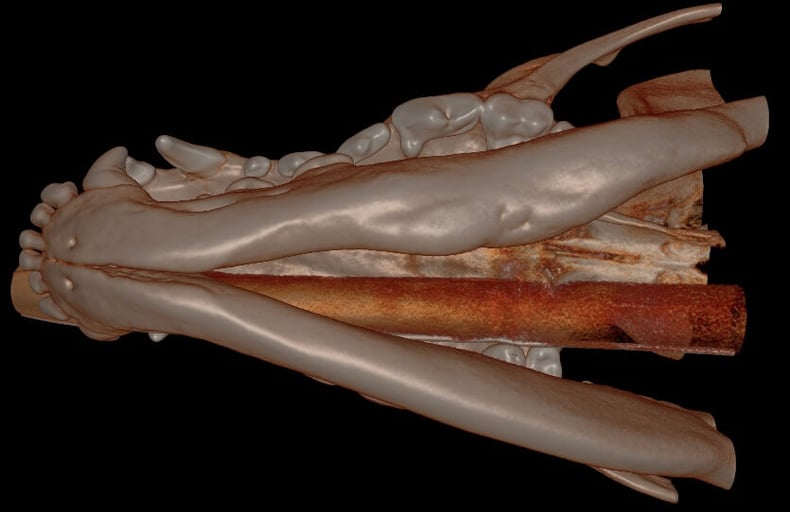

.jpg?width=629&height=390&name=3D%20Hard%20Tissue%20Overview%20(left%20mandible).jpg)

Below: 3D Hard Tissue Lingual View (left mandible)